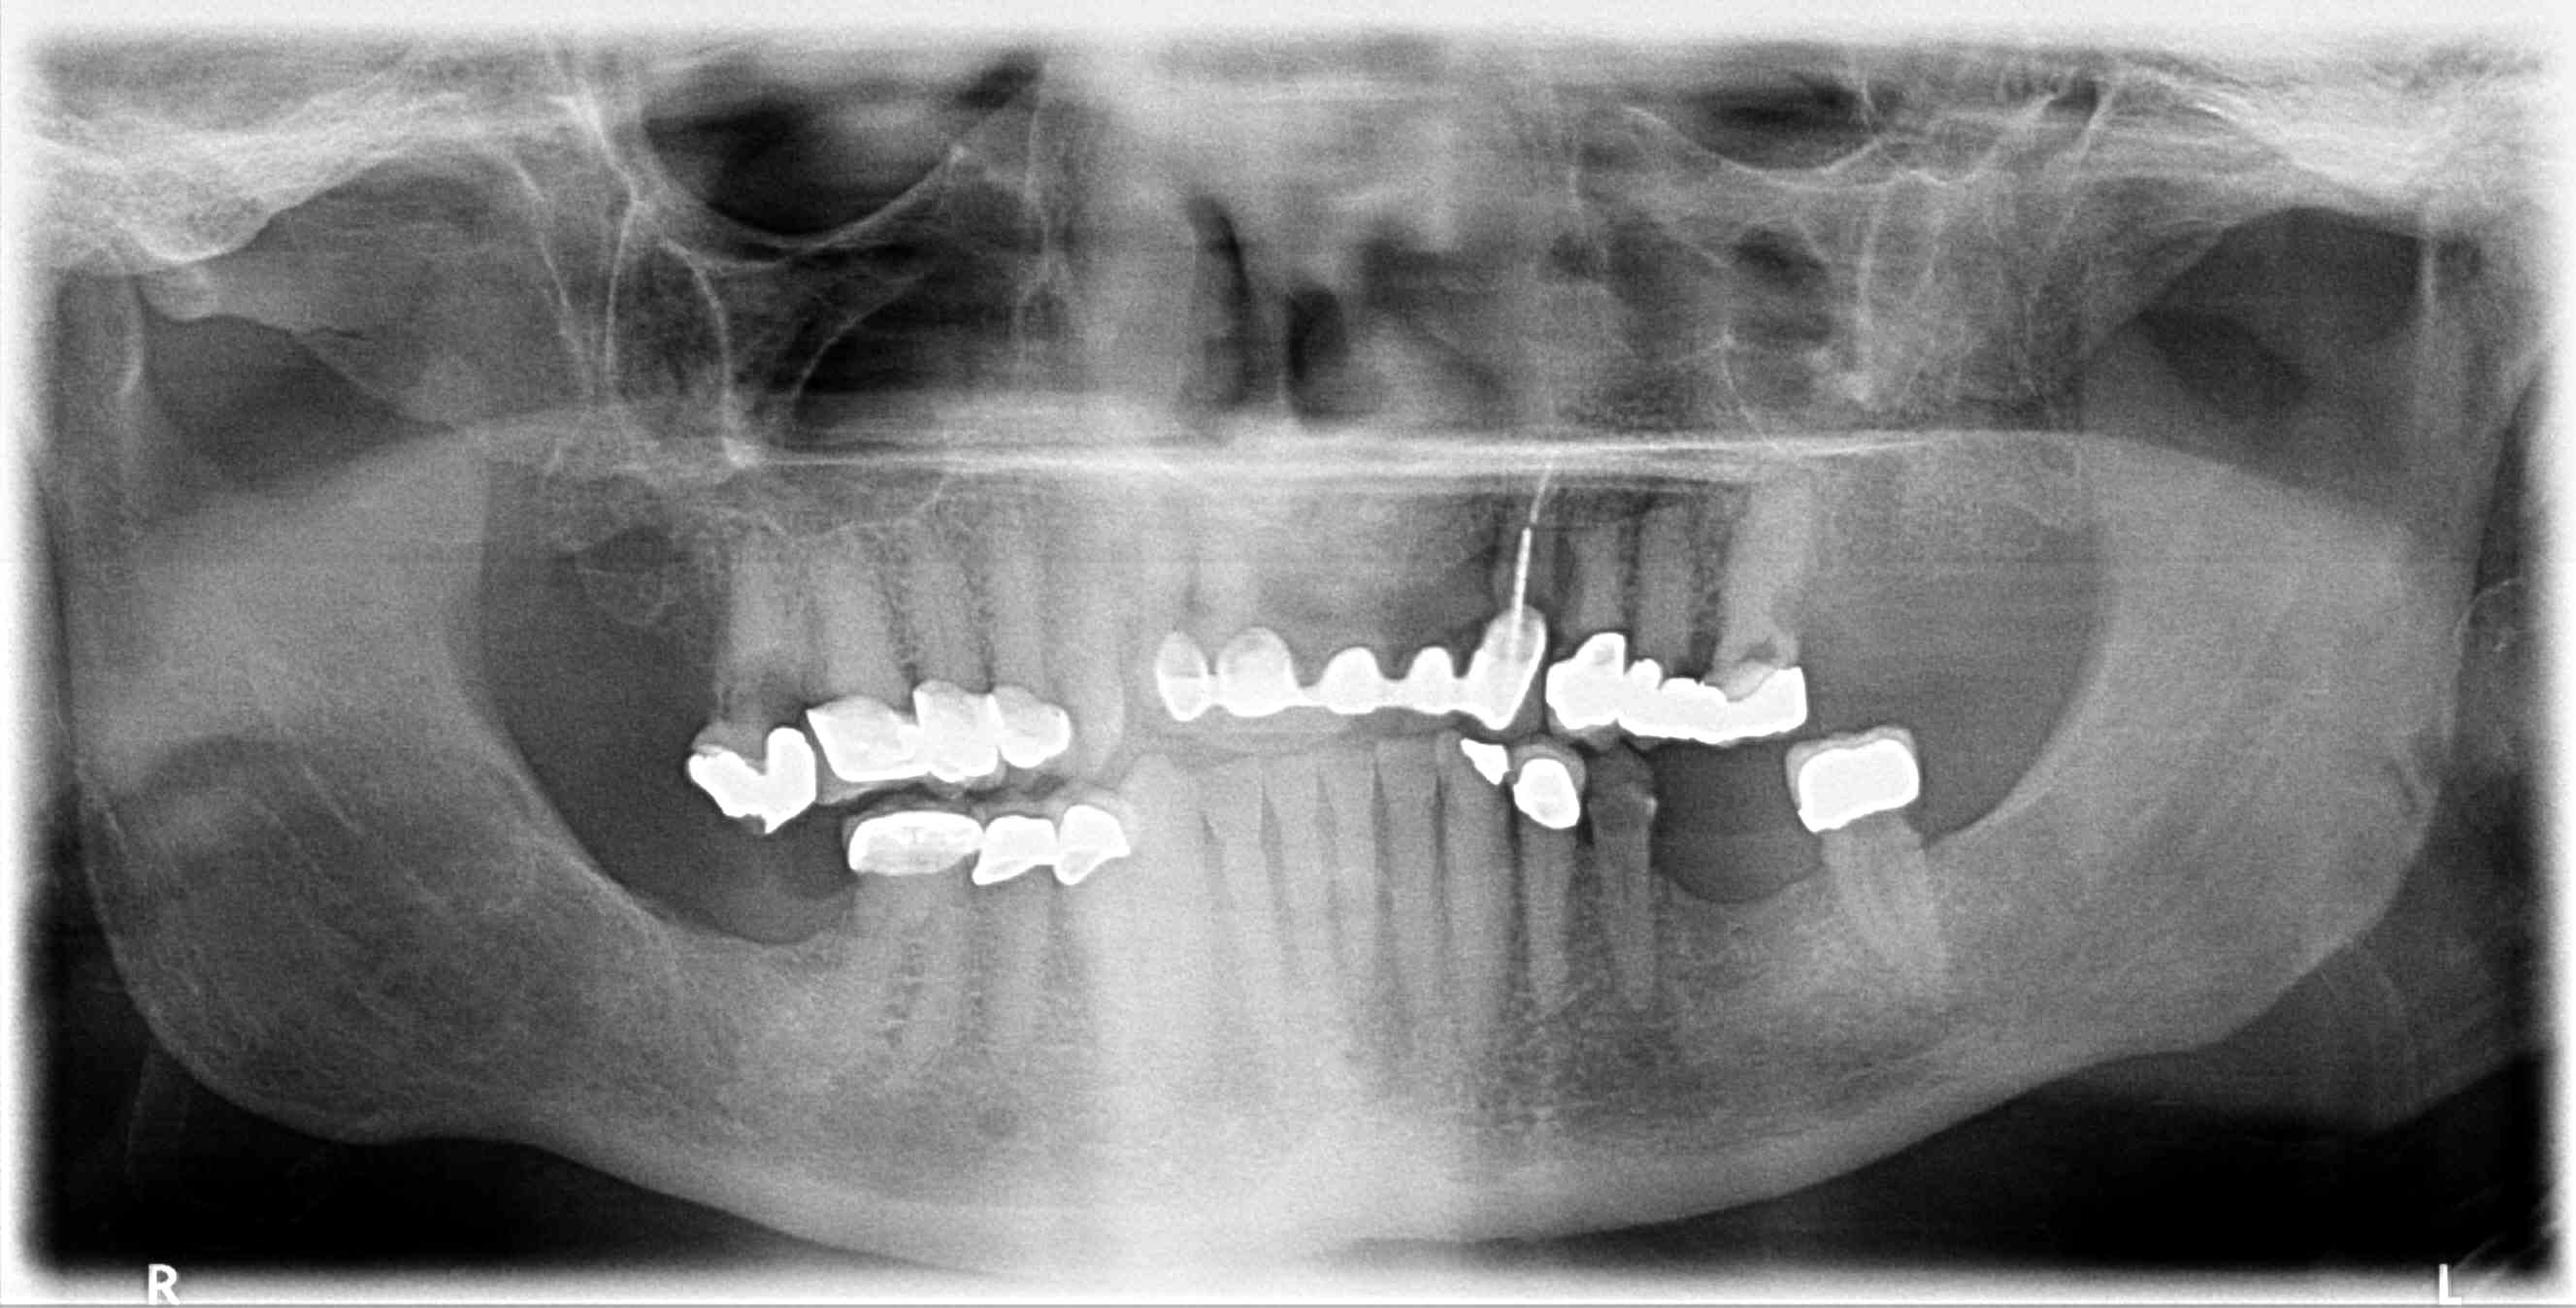

Patient requests ALL ON 4 for both upper and lower arches, complete case fee. X-rays available, taken last week